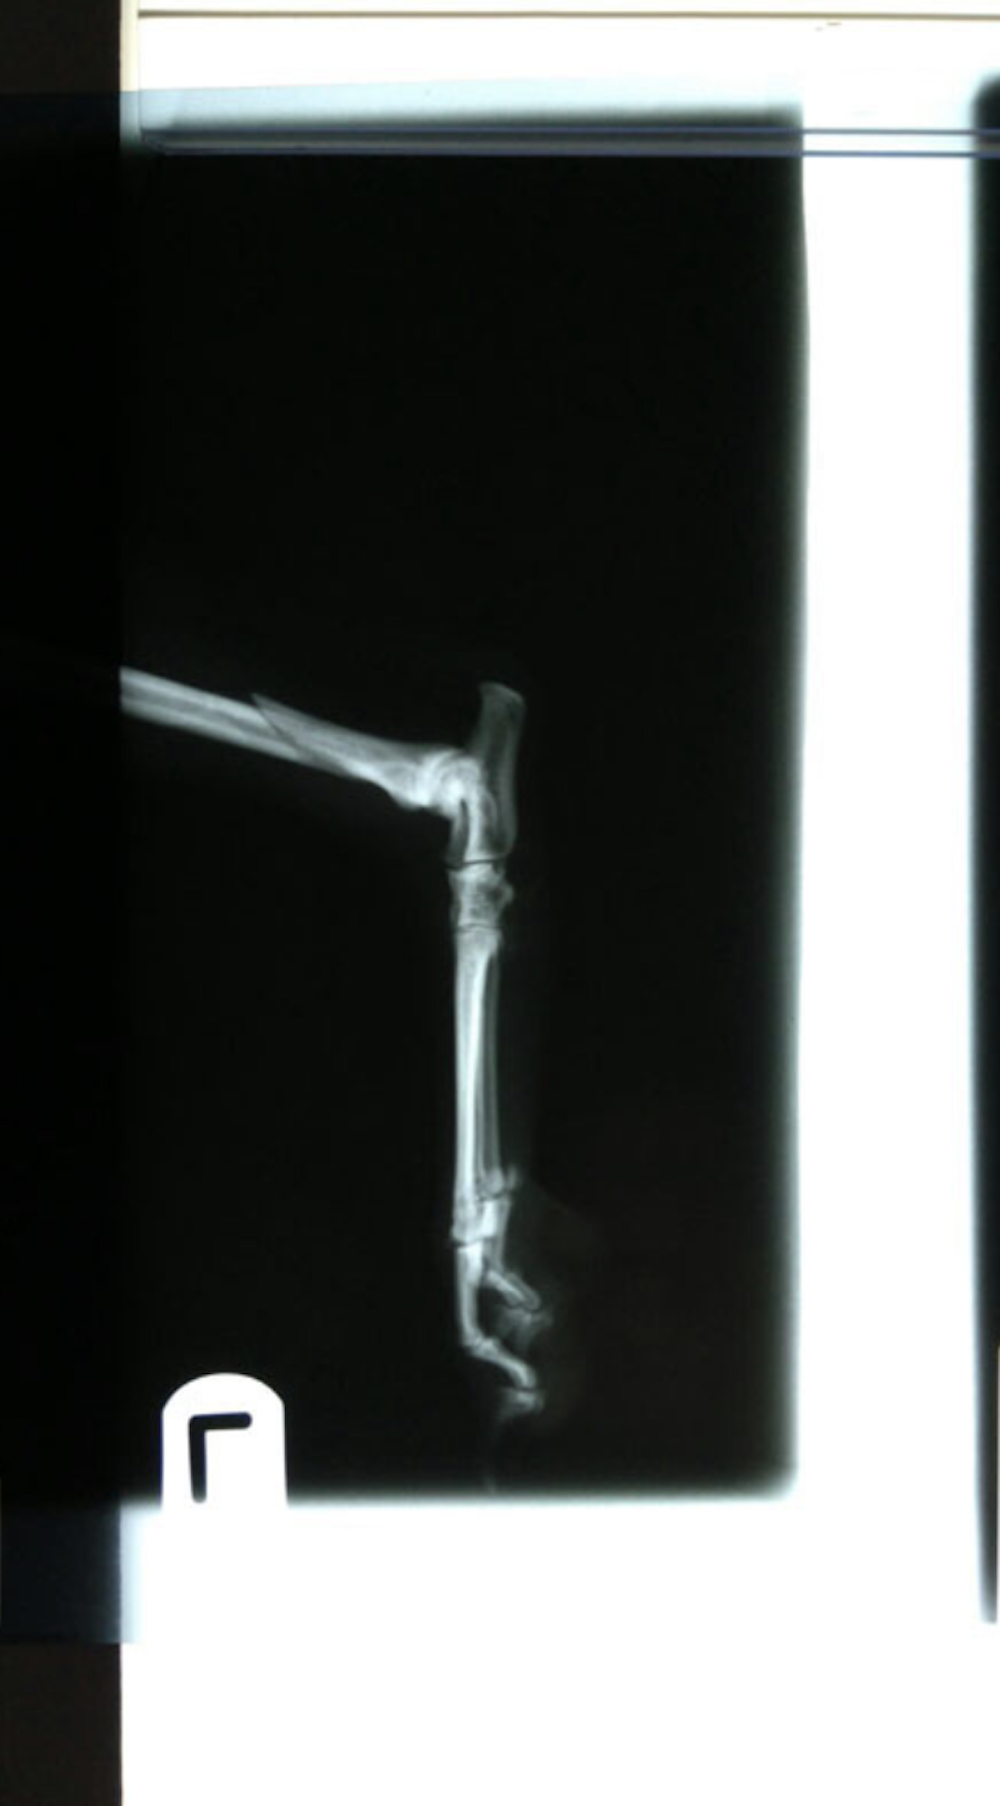

Tibia Fracture Repair